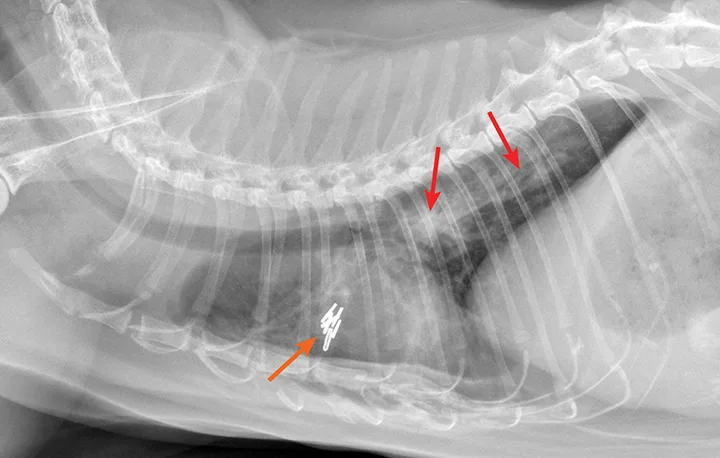

Radiograph of aelurostrongylus abstrusus infection (lungworm). Note the diffuse bronchial pattern (orange arrows), patchy poorly defined soft-tissue nodules (red arrows), and right middle lung lobe alveolar disease (yellow arrow). This pattern could be confused with feline asthma in this case; however, the right middle lung does not appear atelectatic but instead infiltrated. Fine-needle aspiration of the right middle lung lobe confirmed larvae.